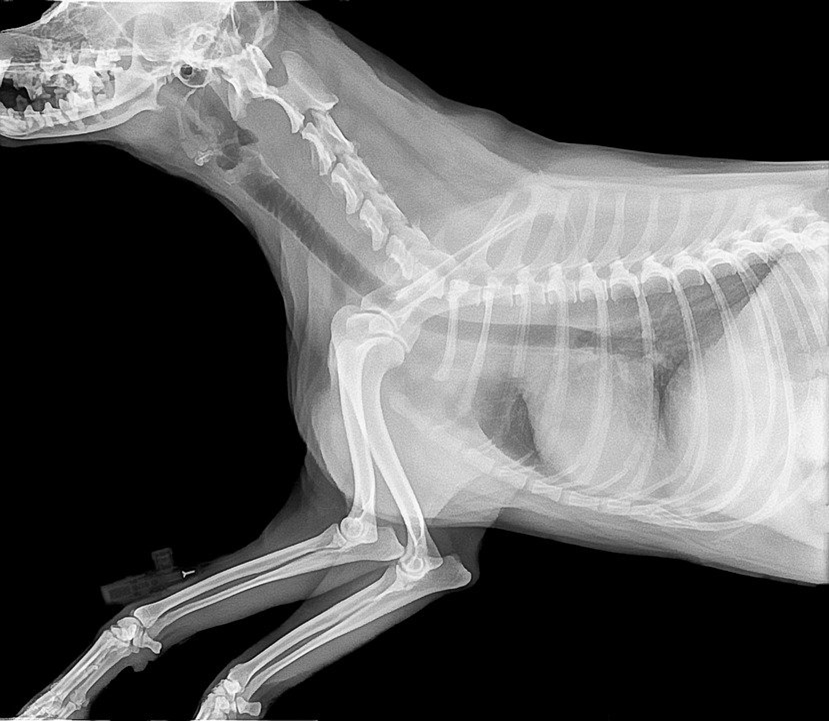

* 개, 강아지 구루병 이란?

강아지도 칼슘, 인, 비타민A, 비타민D가 부족하면 구루병에 걸릴 수 있습니다. 이들 영양소가 부족하면 뼈가 약해지는 증상이 오고 골반의 이상비대와 장곡의 만곡이 일어나서 구루병 증상이 나타난다고 합니다.

* 강아지 구루병이 생기는 이유

강아지 구루병이 생기는 이유는 주로 대형견에서 나타나는데 성장이 빠르게 일어나면서 영양의 불균형에서 나온다고 볼 수 있습니다. 이밖에 생후 2,3개월 강아지에게도 다산으로 인해 어미젖이 부족하거나, 어미젖의 영양분이 부족했을때 구루병이 생길 수 있습니다.

* 강아지 구루병 증상

구루병 증상은 체중이 앞쪽에 쏠려있기 때문에 먼저 앞다리부터 나타나는데 앞다리 발목부분이 굵어지고 발바닥이 벌다리가 바깥쪽으로 휘어지기도 하며, 허리가 굽기도 하는 증상이 나타납니다.

* 강아지 구루병 예방 및 치료

급격한 성장하는 생후 2개월 경에 칼슘과 비타민 섭취에 신경쓰는 동시에 산책으로 햇빛을 쐬 주어야 합니다. 영양가있는 사료와 충분한 햇빛, 약 등으로 치료가 가능합니다.